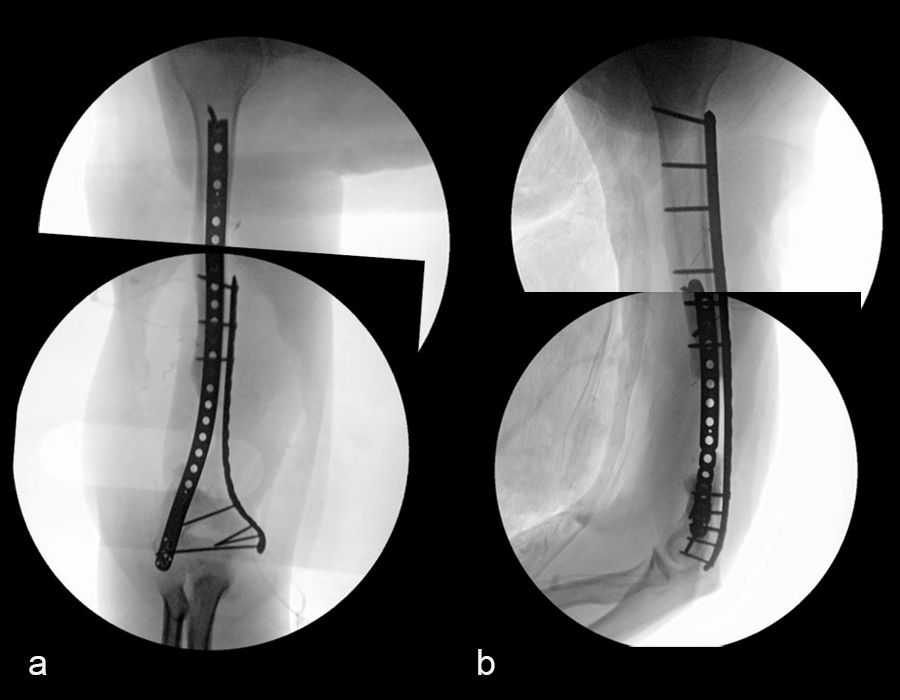

The second stage of surgery took place in October 2022. The cage was inserted (Figs 20-22) and filled with ~20cc autograft obtained by RIA of the femur, 30cc allograft and 3cc BMAC.

Healing progressed well over the following 9 months (Fig 23 - 27). The patient’s pain was well controlled in the early postoperative phase, and he was weaned off the prescribed narcotics after four weeks. He remained smoke free for the first four weeks and then admitted to re-starting his vaping. His elbow ROM improved significantly to 20-125 and good supination/pronation.